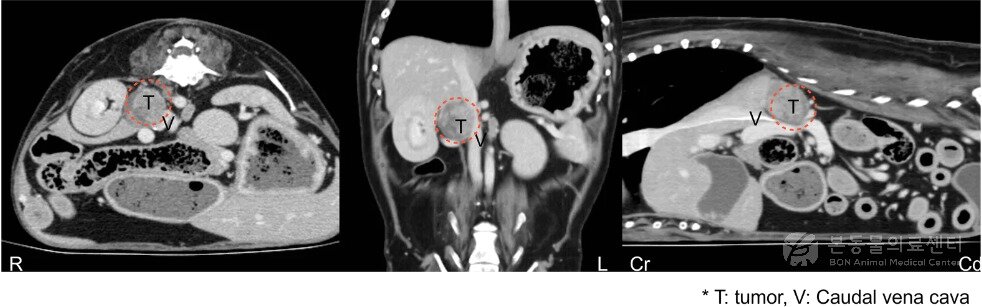

본문 이미지 - 10살 말티즈 CT 검사 결과 확인된 부신 종양(본동물의료센터 제공) ⓒ 뉴스1

10살 말티즈 CT 검사 결과 확인된 부신 종양(본동물의료센터 제공) ⓒ 뉴스1